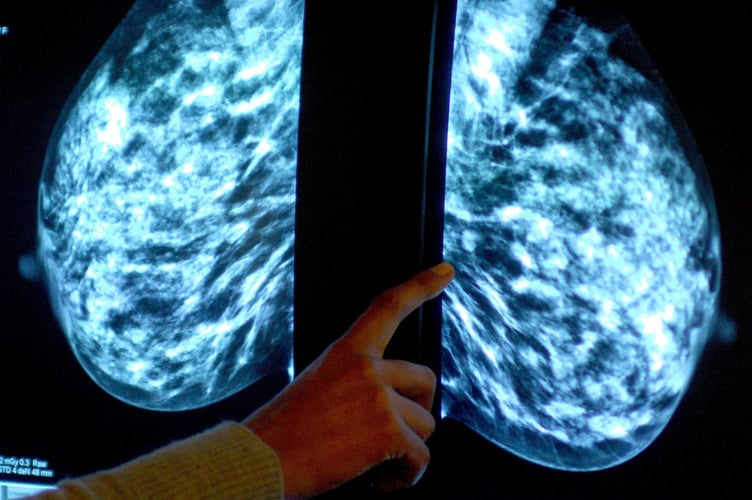

Anyone registered with a GP as female will be invited for NHS breast screening every three years between the ages of 50 and 71.

NHS England figures show 37,735 of the 55,355 people invited for a screening in the former NHS Bath and North East Somerset, Swindon and Wiltshire CCG had a test in the year to March this year.

It meant uptake of the screening stood at 68% – up from 64% the year before, but below pre-pandemic levels of 76% in 2019-20.